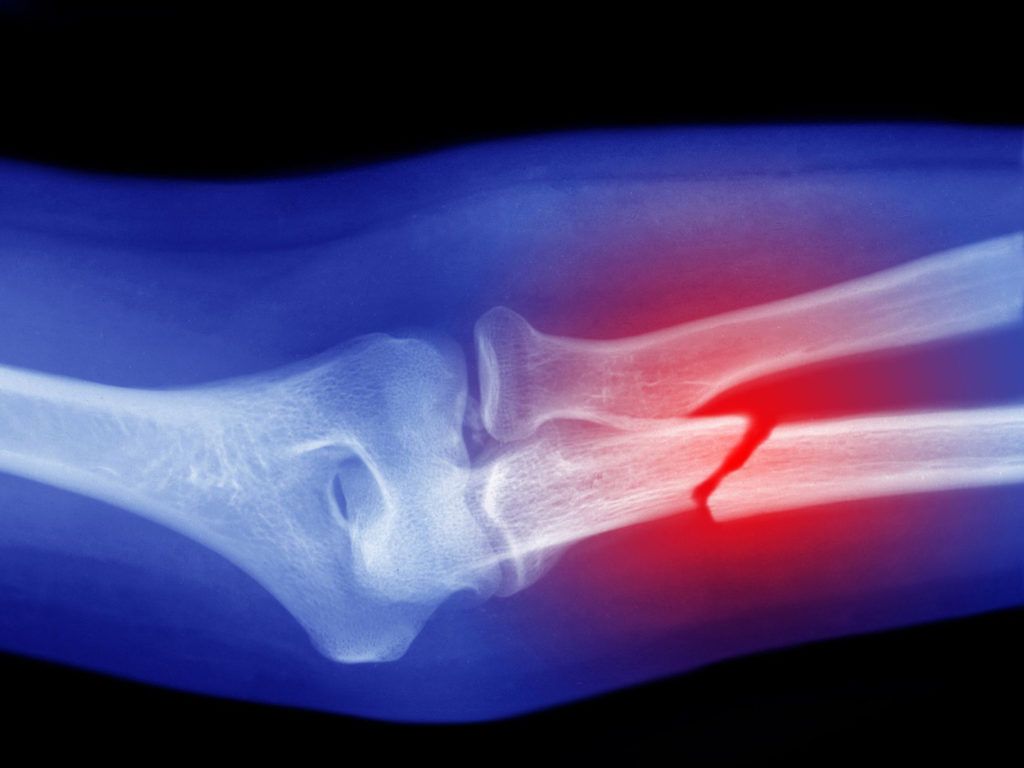

Une fracture se produit lorsqu'un os est cassé ou fêlé sous l'effet d'une pression excessive ou d'un traumatisme. Ces blessures, tout comme d'autres pathologies fréquentes telles que les tendinites, l'arthrose, les entorses et les luxations, touchent aussi bien les plus jeunes, à cause de leurs activités intenses, chocs et chutes, que les plus âgés dont les os deviennent plus fragiles avec l'âge.

Les fractures provoquent des douleurs intenses, un gonflement visible, ainsi que l'apparition d'ecchymoses. Dans certains cas, la zone touchée peut sembler déformée, tordue ou déplacée, ce qui nécessite une prise en charge médicale rapide pour assurer une bonne cicatrisation et éviter les complications. Découvrons ensemble ce sujet en détail.

Les différents types de fractures.

La gravité de cette pathologie varie considérablement selon le type de fracture. Voici les principales catégories :

• Fêlure : petite fissure dans l'os, souvent difficile à détecter sans imagerie médicale.

• Fracture partielle : l'os est cassé en partie mais reste en un seul morceau.

• Fracture totale : l'os est complètement cassé en deux sections distinctes.

• Fracture déplacée : les extrémités de l'os fracturé ne sont plus alignées.

• Fracture fragmentée (ou comminutive) : l'os est brisé en plusieurs morceaux.

• Fracture transversale : cassure nette de l'os, perpendiculaire à son axe.

• Fracture oblique : cassure en biais, souvent causée par une force angulée.

• Fracture en spirale : cassure en torsion autour de l'os, typique des mouvements de rotation.

• Fracture de compressions : écrasement de l'os, fréquent au niveau des vertèbres.